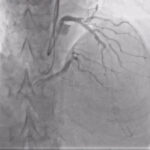

Η διάνοιξη μιας χρόνιας ολικής απόφραξης, όταν πραγματοποιείται σε κατάλληλους ασθενείς και από εξειδικευμένες ομάδες, προσφέρει σημαντικά κλινικά και λειτουργικά οφέλη.

• Ανακούφιση από συμπτώματα στηθάγχης

Μείωση ή εξαφάνιση του θωρακικού πόνου και της δυσφορίας, με αποτέλεσμα την αύξηση της αντοχής.

• Βελτίωση της ποιότητας ζωής

Σημαντική ενίσχυση της καθημερινής λειτουργικότητας του ασθενούς, της ψυχολογικής κατάστασης και μείωση της εξάρτησης από φαρμακευτική αγωγή.

• Αποφυγή χειρουργικής επέμβασης

Η επιτυχής αγγειοπλαστική μειώνει την ανάγκη για αορτοστεφανιαία παράκαμψη, ειδικά σε ασθενείς υψηλού κινδύνου.

• Βελτίωση της πρόγνωσης

Η συμμετοχή της διάνοιξης στη συνολική επαναιμάτωση συμβάλλει στη μείωση των καρδιακών επεισοδίων.